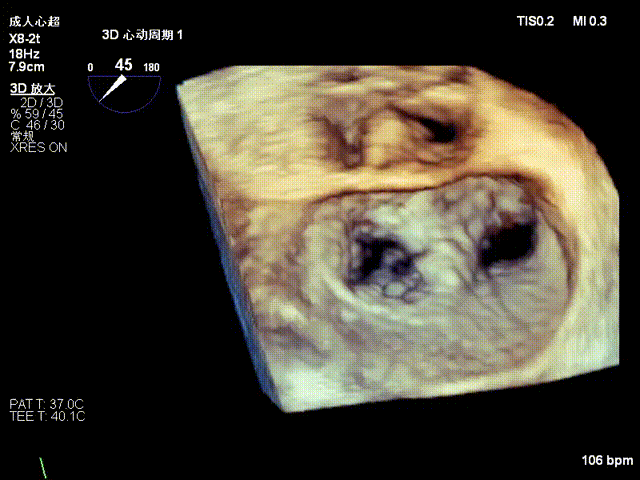

术前3D切面

术前3D上彩